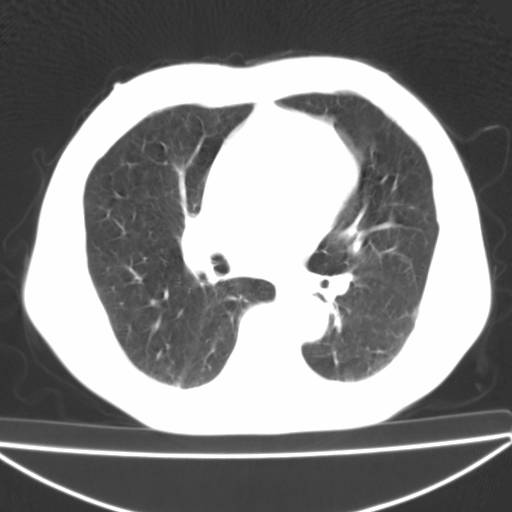

以下是引用zjzjr在2006-12-6 19:04:00的发言:[br]左肺上叶尖后段可见椭圆形高密度影,其内可见点状钙化影,周围可见卫星病灶.首先考虑结核,双侧少量胸腔积液.

以下是引用李世军在2006-12-6 19:54:00的发言:[br]左肺上叶尖后段可见椭圆形高密度影,其内可见点状钙化影,周围可见卫星病灶.首先考虑结核,双侧少量胸腔积液. [br] [br] 双肺轻度肺气肿,左肺上叶后段见多发斑片状密度增高影,周围见少许斑点状卫星病灶,双侧胸膜增厚粘连,纵隔内未见明显改变,考虑结核可能性大,请结合临床或增强扫描. [br] [br]

以下是引用13081830109在2006-12-6 19:35:00的发言:[br]左肺上叶尖后段可见椭圆形高密度影,其内可见点状钙化影,周围可见卫星病灶.首先考虑结核,双侧少量胸腔积液.